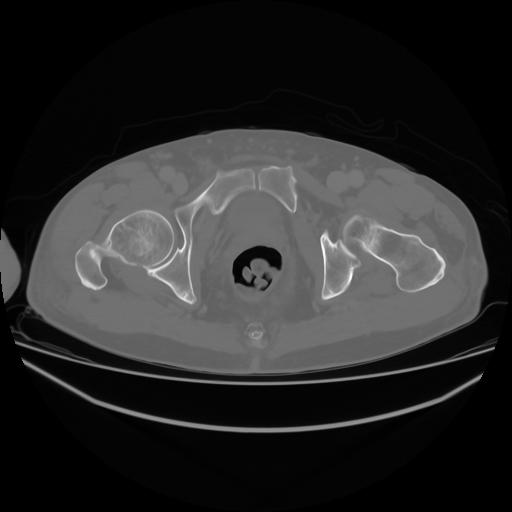

4 CUERPO,CE,Axial,3.0,CUERPO,,